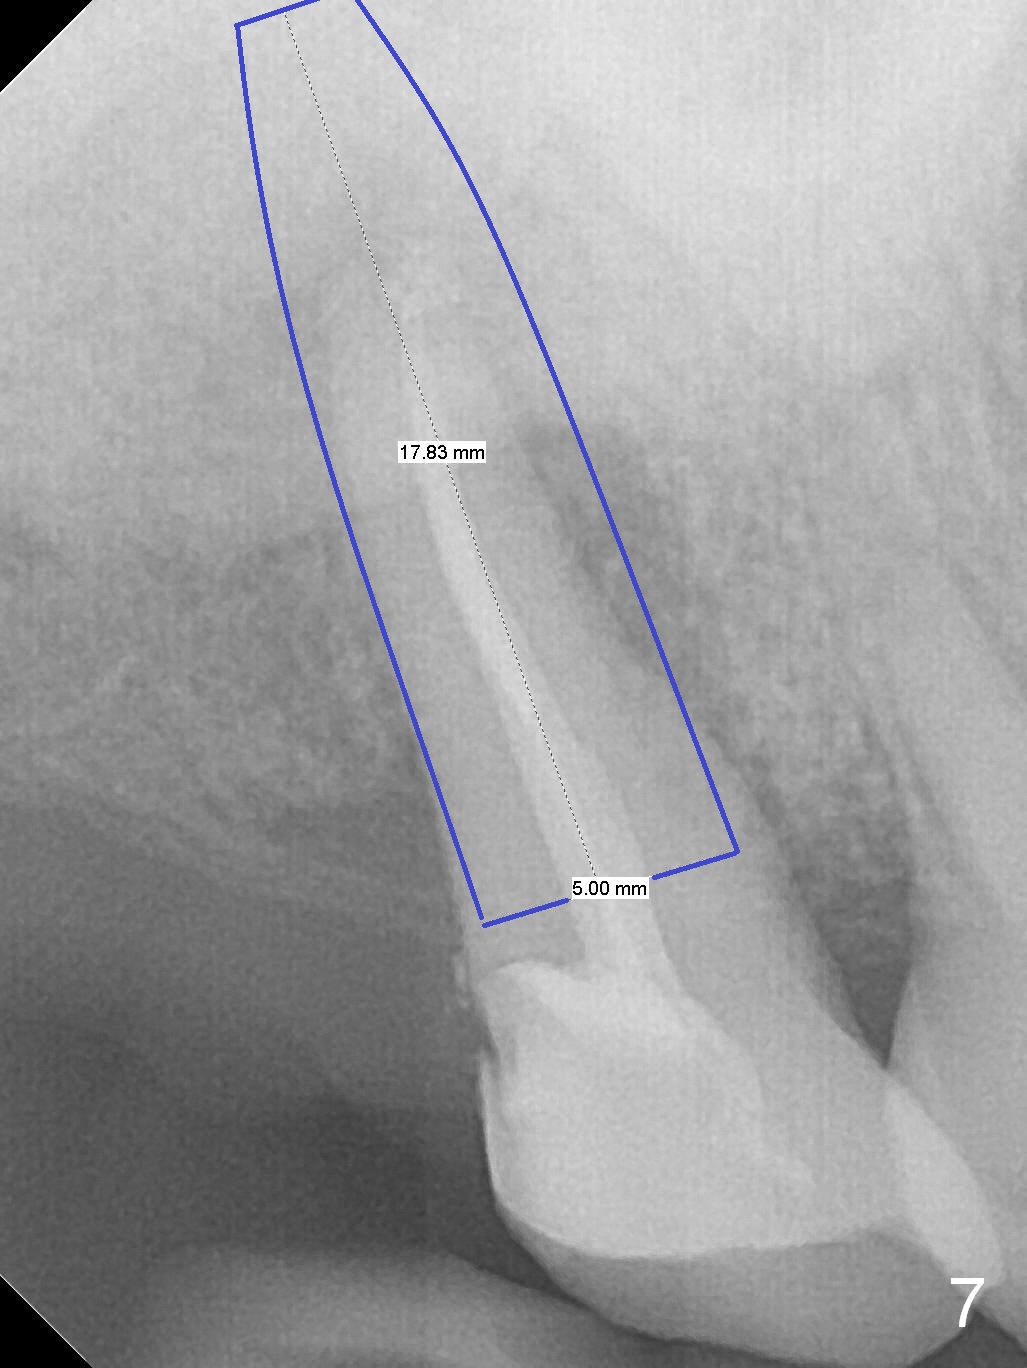

A 52-year-old woman presents to clinic with chief complaint "I can not bite in the upper right". Exam shows DO caries of the tooth #2 (Fig.1). After scaling & root planing and the tooth #1 extraction, pulpotomy is performed at #2. Two months later, pain recurs with swelling. When root canal therapy is finished at #2 (Fig.2-6), the tooth is found to have moderate mobility with guarded to poor prognosis. If the infection does not resolve, extraction and immediate implant seem to be necessary. Considering low bone density around the site of #2, a long implant is indicated (18 mm bone-level, Fig.7,8).